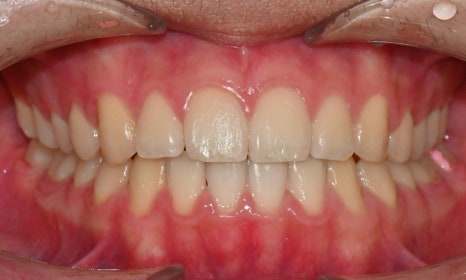

2024.12. 초진 구내사진 - 연세정원치과

치료 시작 7개월 후 사진으로, 치아 배열 후 아래 우측에 미니스크류를 식립하여 치아 중심선을 개선하는 중으로, 교합과 치아 중심선이 많이 개선된 것을 확인할 수 있습니다.

약 1년 간의 교정 치료를 통해 어긋나 있던 치아 중심선이 자연스럽게 맞춰졌고, 중심선 비대칭이 개선 및 하악 아랫입술 돌출도 눈에 띄게 호전되었습니다. 무엇보다 치료 기간 동안 앞니의 치근 흡수는 추가적인 진행 없이 안정적으로 유지되었습니다.

돌출을 조금 더 개선하는 것을 추천했으나, 환자가 갑자기 군 입대를 하게 되어 현 상태로 치료를 마무리하기로 하였습니다. 치료 전후 치아 위아래 중심선이 일치하며 좌우 어금니 교합도 향상되었습니다. 하악 치열의 후방 이동으로 아래 입술의 돌출도도 많이 개선되었습니다. 멀리서도 믿고 내원해주고, 치료 기간 동안 성실히 협조해준 환자분께 감사드리며 앞으로도 건강한 치아로 군 생활 잘 마치길 응원합니다 :)

치료 전후 비교 - 연세정원치과